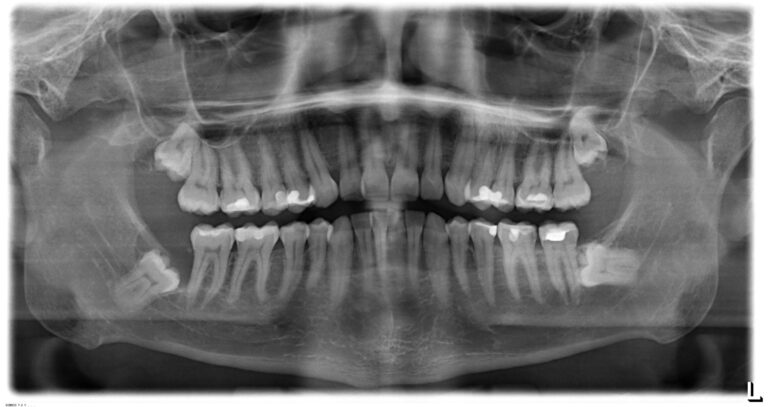

Von Ihrem Zahnarzt oder Kieferorthopäden angefertigte Röntgenbilder sollten Sie zum Beratungsgespräch vor Ihrem Eingriff mitbringen. Gerne können Sie sich zum Operationstag einen Music-Player mitbringen; die meisten Patienten können sich mit ihrer vertrauten Musik entspannen.